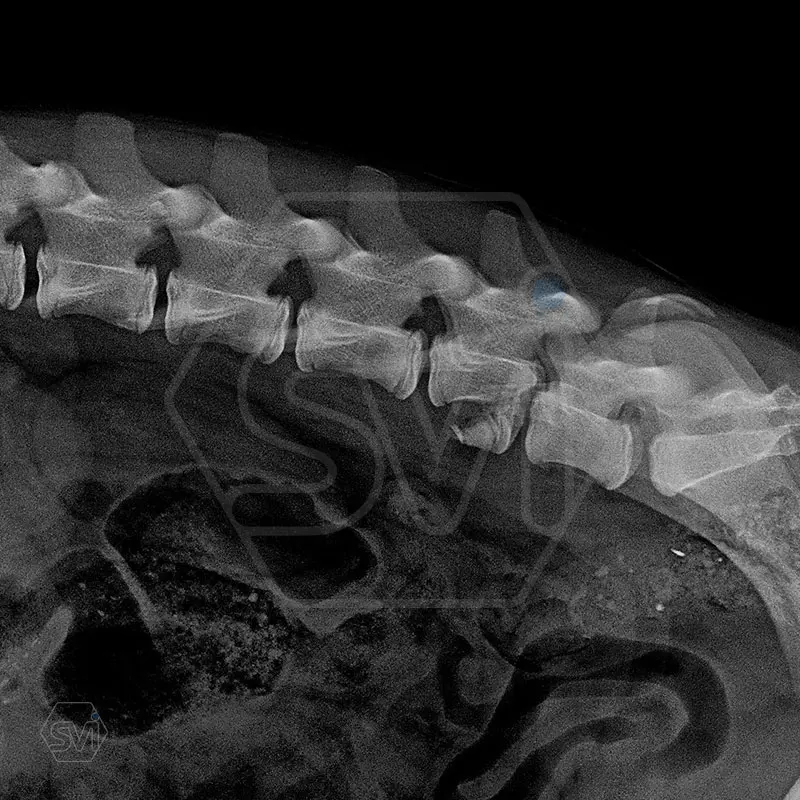

L6 vertebral body fracture fixation with 2.7-mm SOP-LC system

A mixed breed dog, 13 kg, about 8 months old, suffered a car accident and had a fracture of the L6 vertebral body with a mild displacement. (As an additional finding, there was also a fracture of the right radius ulna.) After the accident, his neurological condition was promising.

We performed a laminectomy of L7 and then performed fixation with a 4-4 clamp, bilateral 2.7-mm SOP-LC system. Control x-rays were taken at 6 and 12 weeks after surgery. Based on the video, in our opinion, the dog has recovered… :)